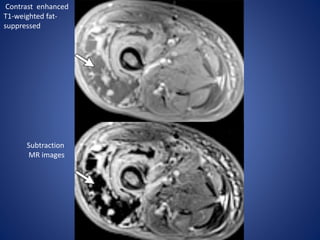

Contrast enhanced

T1-weighted fat-

suppressed

Subtraction

MR images

• #9  Axial T1-weighted (a) and T2-weighted fat-suppressed (b) MR images of the thighs reveal subcutaneous, fascial, and intramuscular edema and muscle enlargement, findings that are most pronounced in the right anterior compartment. The asymmetric distribution of the findings and the involvement of noncontiguous muscles are characteristic of this condition

• #10 (c, d) Contrast material–enhanced T1-weighted fat-suppressed (c) and subtraction (d) MR images show patchy peripheral enhancement with central nonenhancement and serpentine areas of signal void in the right vastus lateralis muscle (arrow). Symptoms resolved with conservative management, which included glycemic control and analgesics; no antibiotics were administered.